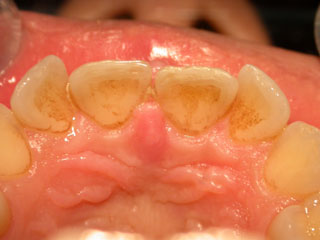

Foto scattata al termine del trattamento tramite laser

Siamo intervenuti con il laser a diodi in maniera radicale eliminando la tumefazione sul palato e il frenulo con tutto il tessuto fibro-granulomatoso presente tra i denti; la paziente è stata liberata dal tessuto che interferiva con l’occlusione degli incisivi inferiori.